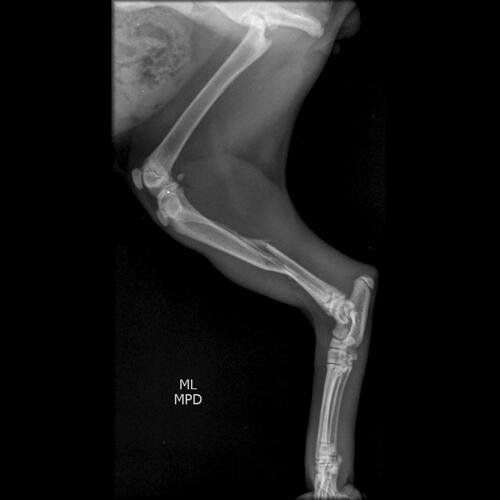

Um gatinho de rua foi atropelado em frente de casa e levamos o gatinho pro veterinario e ele encaminhou pro ortopedista e precisa fazer cirurgia urgente!! Pois ele teve 3 fraturas na perna e no fêmur.. Estamos desesperados e nao temos condições de pagar, e por esse motivo estamos fazendo essa vakinha para que ele possa voltar a andar.